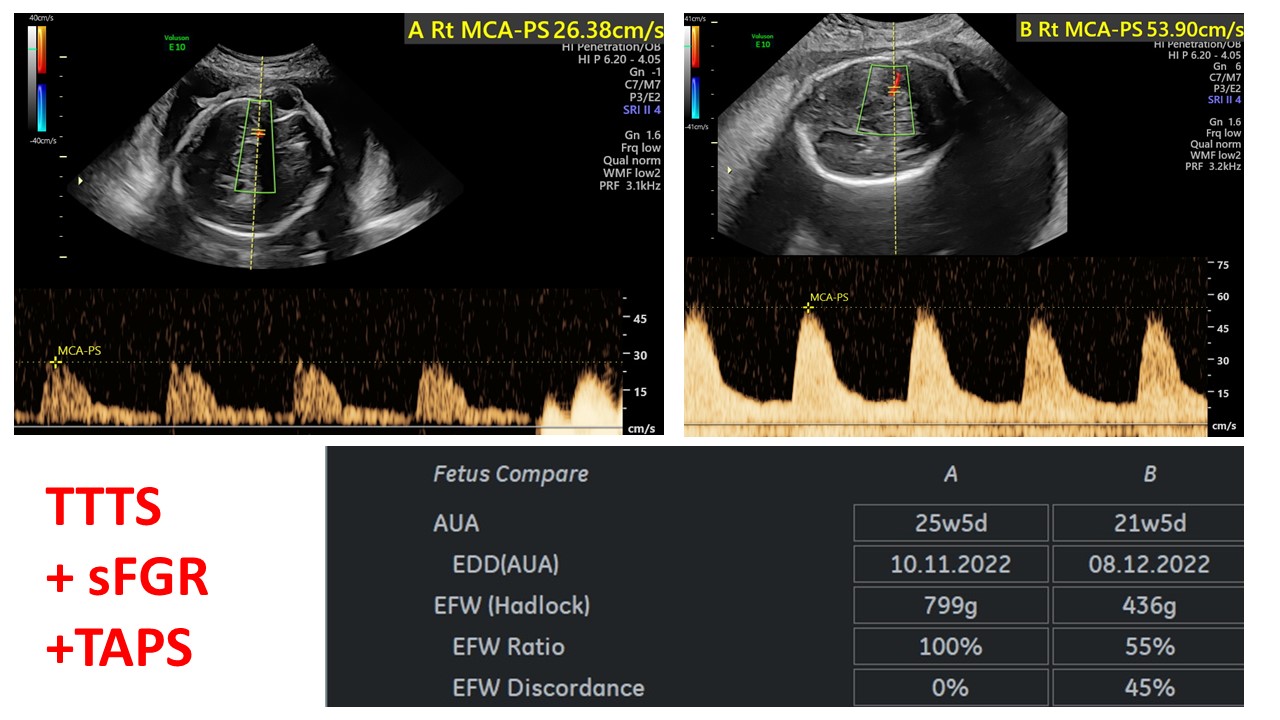

Cập nhật chẩn đoán và xử trí đa thai

BS Hà Tố Nguyên - Trung tâm Y học Bào Thai BV Đa khoa Tâm Anh TPHCM